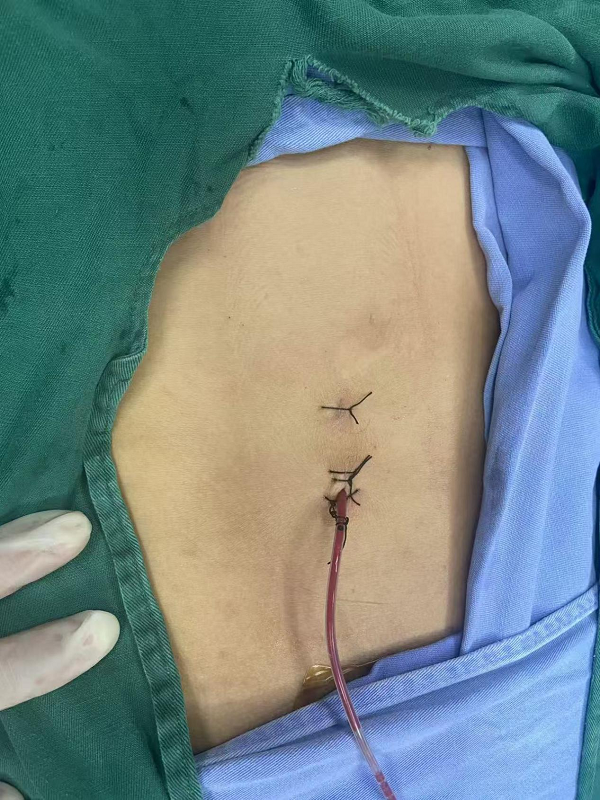

单孔腹腔镜下阑尾切除术(SILA):患者为年轻女性,既往产后1周因粪石性阑尾炎在我院胃肠外科保守治疗。此次因“再转移性右下腹痛9小时余”入院,经查体、实验室检查及腹部影像学评估,明确诊断为急性阑尾炎,具备手术指征。考虑到患者为年轻女性,对术后腹部美观度要求较高,胃肠外科王林财主治医师、丁洪根主治医师经充分评估病情、完善术前准备后,决定给予行单孔腹腔镜手术方案。

手术在全麻醉下进行,团队仅通过患者脐部一个约2cm的微小切口,置入单孔腹腔镜器械,在高清腹腔镜视野下精准分离阑尾系膜、结扎阑尾根部,完整切除病变阑尾,并将标本经脐部切口取出,随后对切口进行美容缝合。整个手术操作精细、出血极少,手术时间短,成功规避了传统多孔腹腔镜手术的多个切口创伤,目前患者已顺利康复出院。